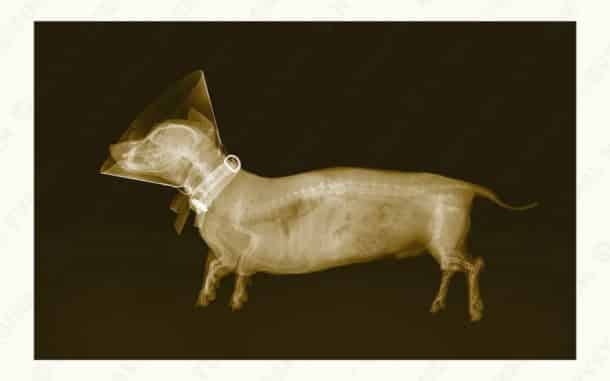

Le corps humain vu aux rayons X ! Vraiment bluffant…

Et pas que le corps humain…